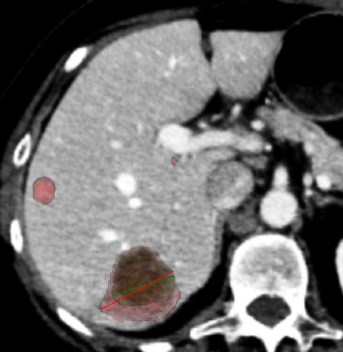

Ce travail s’intéresse à une problématique très concrète de la pratique quotidienne en imagerie oncologique : la mesure des lésions tumorales. En pratique clinique, l’évaluation de la réponse aux traitements repose largement sur les critères RECIST, qui utilisent le diamètre maximal des lésions cibles pour apprécier l’évolution de la maladie. Ces mesures, pourtant centrales dans la prise en charge des patients, restent aujourd’hui réalisées manuellement par les radiologues. Or, plusieurs études ont montré qu’elles peuvent présenter une variabilité entre lecteurs, notamment selon l’expérience du radiologue ou la morphologie des lésions.

Dans ce contexte, l’objectif de notre étude était d’évaluer un outil d’intelligence artificielle capable de segmenter automatiquement les métastases hépatiques au scanner et d’en extraire différentes mesures, notamment les diamètres compatibles avec les critères RECIST. Nous avons comparé ces mesures à celles réalisées par des radiologues ayant différents niveaux d’expertise afin d’en analyser la concordance et la variabilité.

Les résultats montrent que les diamètres mesurés automatiquement par l’IA sont très proches de ceux obtenus par les radiologues et, surtout, qu’ils se situent dans l’intervalle de variabilité habituellement observé entre lecteurs. Autrement dit, l’intelligence artificielle ne semble pas introduire de variabilité supplémentaire, mais reproduit plutôt les dynamiques de mesure observées entre radiologues. Ces résultats suggèrent que ces outils pourraient contribuer à standardiser les mesures utilisées pour le suivi des patients en oncologie tout en simplifiant certaines étapes du workflow.